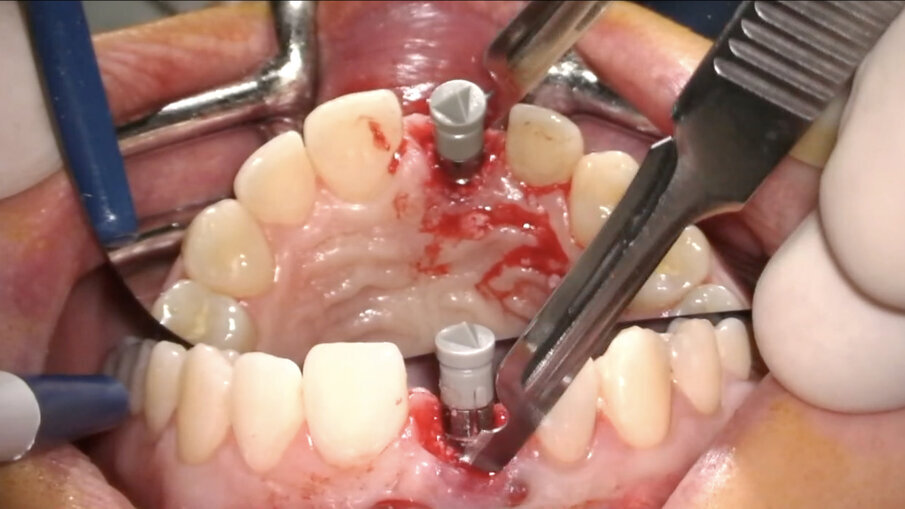

- Posizionamento implantare

L’impianto (XIVE – Dentsply Sirona) è stato posizionato centralmente con un’inclinazione palatale al fine di evitare che il foro di accesso della vite cadesse sul margine incisale del provvisorio o, ancor peggio, sulla sua superficie vestibolare. Il gap osseo vestibolare è stato riempito con Geistlich Bio-Oss (Geistlich Pharma) (Figg. 16-19).

- Personalizzazione matrice “FIBRO-GIDE”

Geistlich Fibro-Gide (Geistlich Pharma) è una matrice in collagene di origine suina, porosa, riassorbibile e volumetricamente stabile, progettata specificatamente per la rigenerazione e l’aumento dei tessuti molli al fine di evitare il prelievo autologo di tessuto connettivo. Tale matrice, usata in guarigione sommersa, favorisce l’angiogenesi, la formazione di nuovo tessuto connettivo e permette la stabilità volumetrica dei tessuti, ripristinando la corretta ampiezza biologica1-11. In un caso estetico come questo, la matrice va personalizzata e adattata al sito ricevente. Essendo molto stabile e mantenendo il suo volume in fase di guarigione non va, infatti, sovradimensionata per evitare trazioni del lembo e/o volumi eccessivi a guarigione avvenuta; non deve essere inoltre eccessivamente compressa dal lembo in modo che possa mantenere la sua originale struttura reticolare interna. Trattandosi di una matrice particolarmente resistente quando asciutta, suggerisco di modellarla utilizzando una fresa in zirconia a bassi giri (KOMET): in tal modo, infatti, si riesce a modellarla in modo preciso, evitando comunque il surriscaldamento e la denaturazione del collagene mantenendo le sue caratteristiche strutturali inalterate (Figg. 20, 21).

- Posizionamento della matrice e sutura

La matrice va posizionata nella tasca mucosa creata in precedenza (Fig. 22). Nel caso in cui siano state eseguite incisioni, i tessuti molli devono essere ermeticamente suturati sopra di essa, mentre, nel caso opposto, deve essere delicatamente inserita in modo tale da sommergerla completamente.